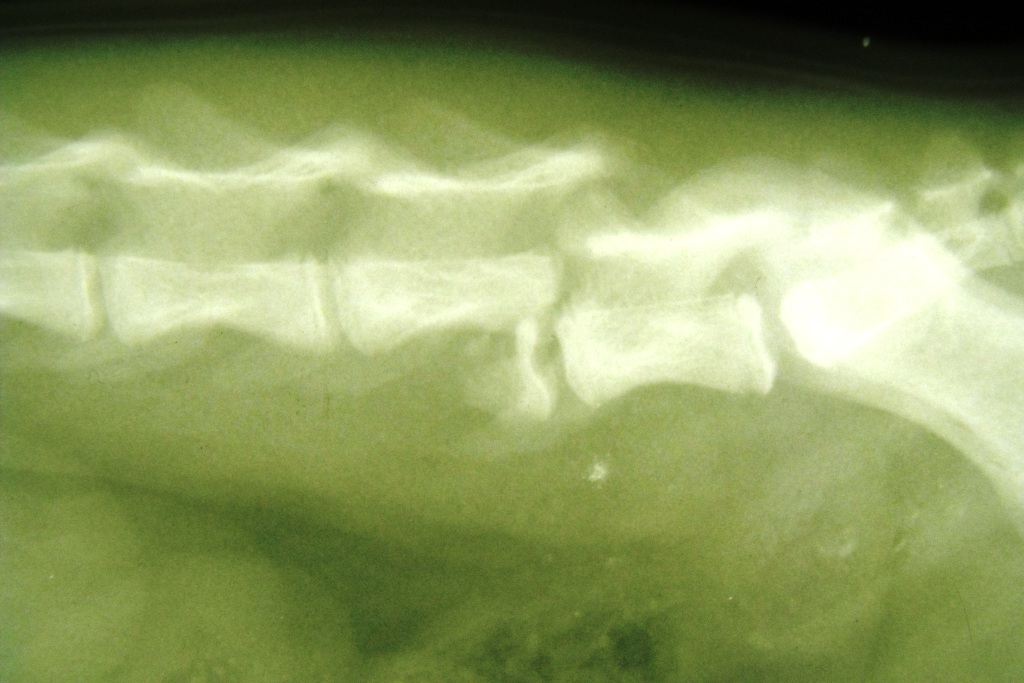

Manchmal gibt es Dinge, die man kaum fassen kann. Nach einem Autounfall wurde mir

eine kleine Katze mit einem Bruch eines Lendenwirbels vorgestellt. Trotz der massiven Verschiebung des Wirbels war sie nicht vollständig gelähmt. Auf besonderes Drängen des Besitzers konnte ich die Wirbelsäule wieder zurückdrehen und, zwar relativ einfach, aber effektiv mit einem Draht und einer Schraube fixieren. Tatsächlich ist es so die dass Katze eín fast normales Leben führen kann und auch schon wieder Bäume erklettert.

Keiner hätte das für möglich gehalten bei dem Röntgenbefund.